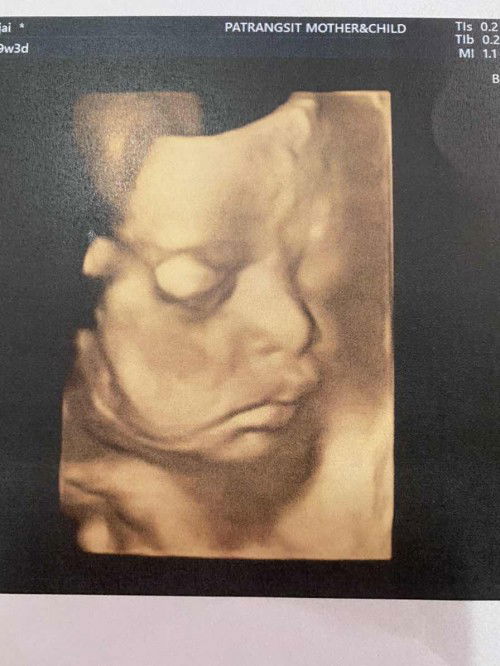

พรุ่งนี้ผ่าคลอด 5/11/65 ☺️ 38W5d

ขอกำลังใจจากแม่ๆด้วยค่ะ #ท้องแรก วันที่30/10 ไปตรวจปากมดลูก มดลูกยังไม่เปิด(ไม่ได้กระตุ้น) แต่นัดไปตรวจอีก 6/11/65 แม่เลยตัดสินใจขอผ่าเลย #อยากเจอแย่แร้วลูก กำหนดคลอดจริงๆ 14/11/65☺️